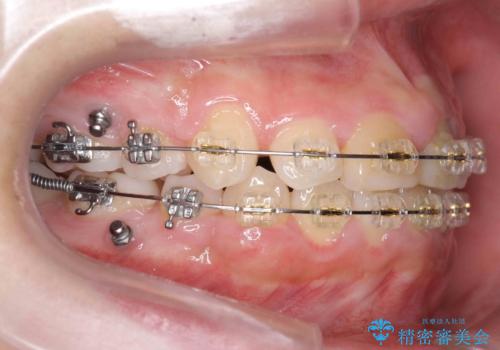

- プラスチック装置

神経の治療を先に行い、ワイヤー矯正を行いました。

上下の小臼歯を抜歯しています。